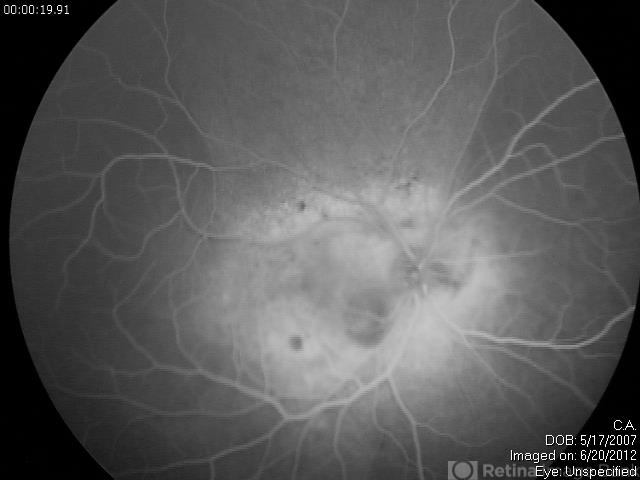

- diffuse choroidal hemangioma

- Fundus camera

- RetCam fluorescein angiogram late venous phase of diffuse choroidal hemangioma